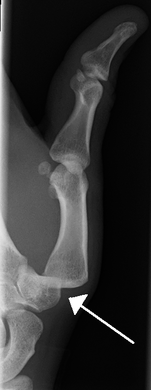

Radiograph of right fifth phalanx bone dislocation- Radiograph of left index finger dislocation

Radiograph of right fifth phalanx dislocation resulting from bicycle accident- Right fifth phalanx dislocation resulting from bicycle accident